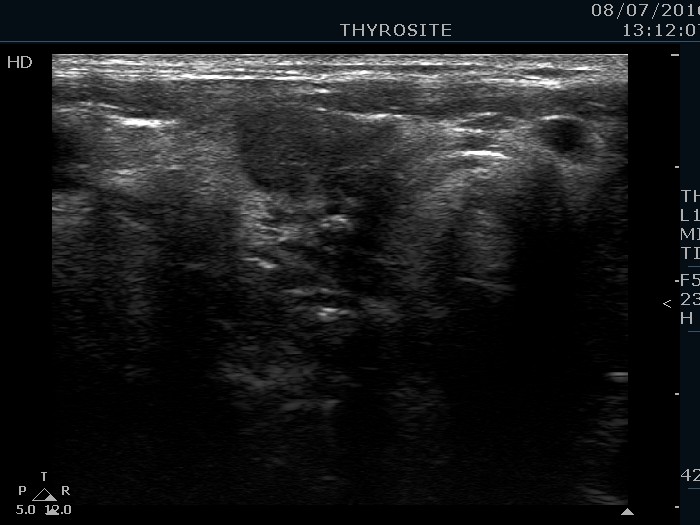

Study on extrathyroidal spread of papillary carcinoma - Case 69. (ultrasonographic picture 5)

Right lobe, another longitudinal scan.